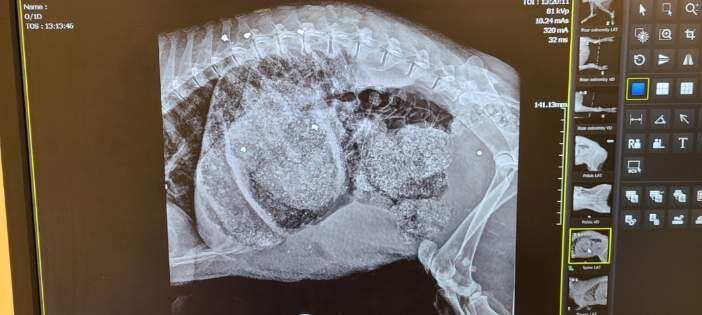

Another X-ray view of the wounds to the javelina.